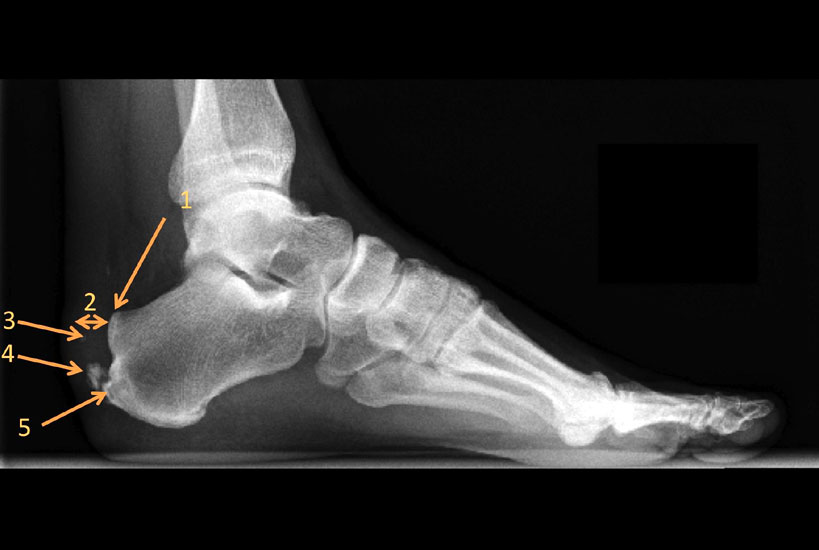

Röntgen

Das konventionelle Röntgenbild ist nach wie vor eine wichtige Orientierungshilfe zur Beurteilung der Beschwerden. Hierbei ist das belastete seitliche Röntgenbild des gesamten Fußes der Standard. Bei Fußfehlstellungen sollten zusätzlich ein belastetes  Röntgen des Fußes d.p., des OSG a.p., sowie eine Rückfußaufnahme (nach Saltzman) durchgeführt werden.

Anhand des seitlichen Fußröntgenbildes kann der Calcaneus-Boden Winkel und die Prominenz der Tuberositas des Calcaneus bestimmt werden und durch das Zusammenspiel dieser beiden Parameter die mögliche Irritation der Achillessehne durch die knöcherne Anatomie beurteilt werden. Bis heute hat sich jedoch kein Parameter etabliert, anhand dessen eine klare Abgrenzung von pathologischen Fehlstellungen möglich ist. Einzelne Arbeiten  zeigen jedoch eine Korrelation der parallel „Pitch-Linien“ und des „Chaveau-Liet“ Winkels  10 zu der Erkrankung (Abb. 2).

Abbildung 3: Das seitliche belastete Röntgenbild des Fußes zeigt die Pathologien des Achillessehnenansatzes: Retroachilläre Bursitis, die den Karger´schen Fettkörper verdrängt (1), Verdickung der Achillessehne (2), intratendinäse Calcifikationen (3), Trak

Abbildung 3

Außerdem lässt sich auf dem seitlichen Röntgenbild im Bereich der Weichteile häufig als indirektes Zeichen der retroachillären Bursitis eine Aufhellung am Achillessehnenansatz erkennen 11. Des Weiteren ist auf die Ausbildung des retrocalcanearen Recessus und die relative Dicke der Achillessehne zu achten 10. Im Bereich der Achillessehne ist auf einen Traktionsosteophyten, der aus Verknöcherungen im Bereich des Sehnenansatzes durch Mikrotraumatisierungen entsteht  sowie intratendinöse Verkalkungen/-knöcherungen zu achten (Abb. 3).